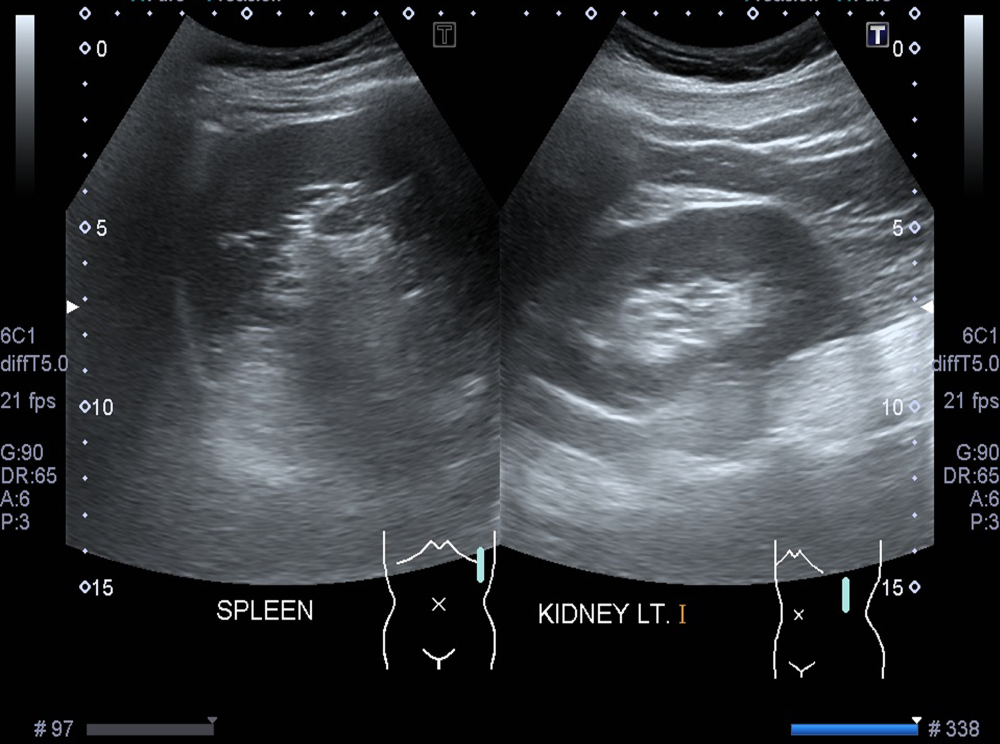

- Прикладывание и перемещение датчика ультразвукового аппарата по коже в области левого верхнего квадранта живота. Этот процесс позволяет получить изображение селезенки на экране компьютера, врач может изменять угол и глубину сканирования, чтобы получить подробное представление об органе.

- Специалист, проводящий обследование, оценивает размер, форму и структуру селезенки, фиксирует показатели и при необходимости сохраняет отдельные снимки.

Фотогалерея